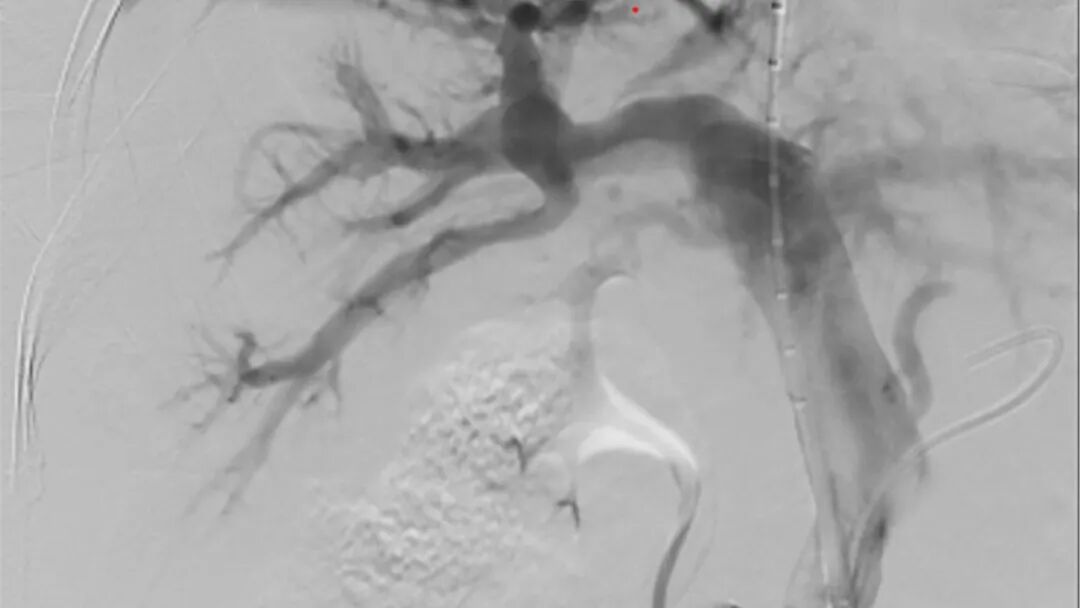

2025年4月29日,玉溪市中山医院肿瘤诊疗中心在中山大学附属第一医院肿瘤介入科主任李家平的指导下,通过多学科协作,成功完成玉溪地区首例经颈静脉肝内门体静脉分流术(TIPS)。这项被誉为介入手术“天花板”的技术,专门攻克肝硬化门静脉高压引发的食管胃底静脉曲张破裂出血、顽固性腹水等棘手病症,为终末期肝病患者搭建起一条关键的“生命通道”。

手术当晚,挑战超乎想象。术中,李家平教授发现赵先生的肝脏严重萎缩,血管扭曲变形,门静脉右支被血栓堵了90%,操作空间极为狭小。李家平教授当机立断,决定从左支突破,但左支的血管又细又与门静脉紧密相邻,稍微扎偏一点就可能导致严重出血。关键时刻,李家平教授凭借精湛的技术和丰富的经验,像穿针引线一样,精确地从肝右静脉精准“穿针”到门静脉左支矢状部,每一个动作都精准无误,成功架起支架。

李家平教授介绍道:“TIPS 手术就像给压力过大的水管开了个 “泄洪口”,既能缓解门静脉压力,又能控制出血、促进腹水吸收。相比传统外科手术,它创伤小、恢复快,患者局麻就能完成手术,几天就能出院。”